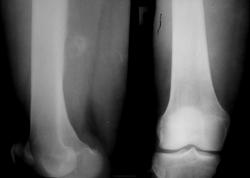

Молодая женщина 25 лет. Жалобы на боли по задней поверхности бедра. Травма была. но этой зимой. По некоторым мнениям - обызествленная гематома.

Действительно, по R-грамме производит впечатление обызвествлённой гематомы. Я не занимаюсь КТ, но на представленных сканах это образование по плотности как кость ( оссифицирующий миозит?). Не знаю, возможно ли это в ваших услових, но можно рекомендовать УЗИ области бедра.

По вот этому срезу у меня складывается впечатление, что этот участок связан с костью - экхондрома? параоссальная хондрома? образование мягких тканей (фиброма)? Мне кажетс, что для того, чтобы обызвествилась гематома травма должна быть давненько, поэтому для меня обызвествленная гематома под большим вопросом.

2.Если это обызествленная гематома то. к чему реакция периоста, да еще и ТАКАЯ. да и мягкотканный компонент присутствует вокруг.